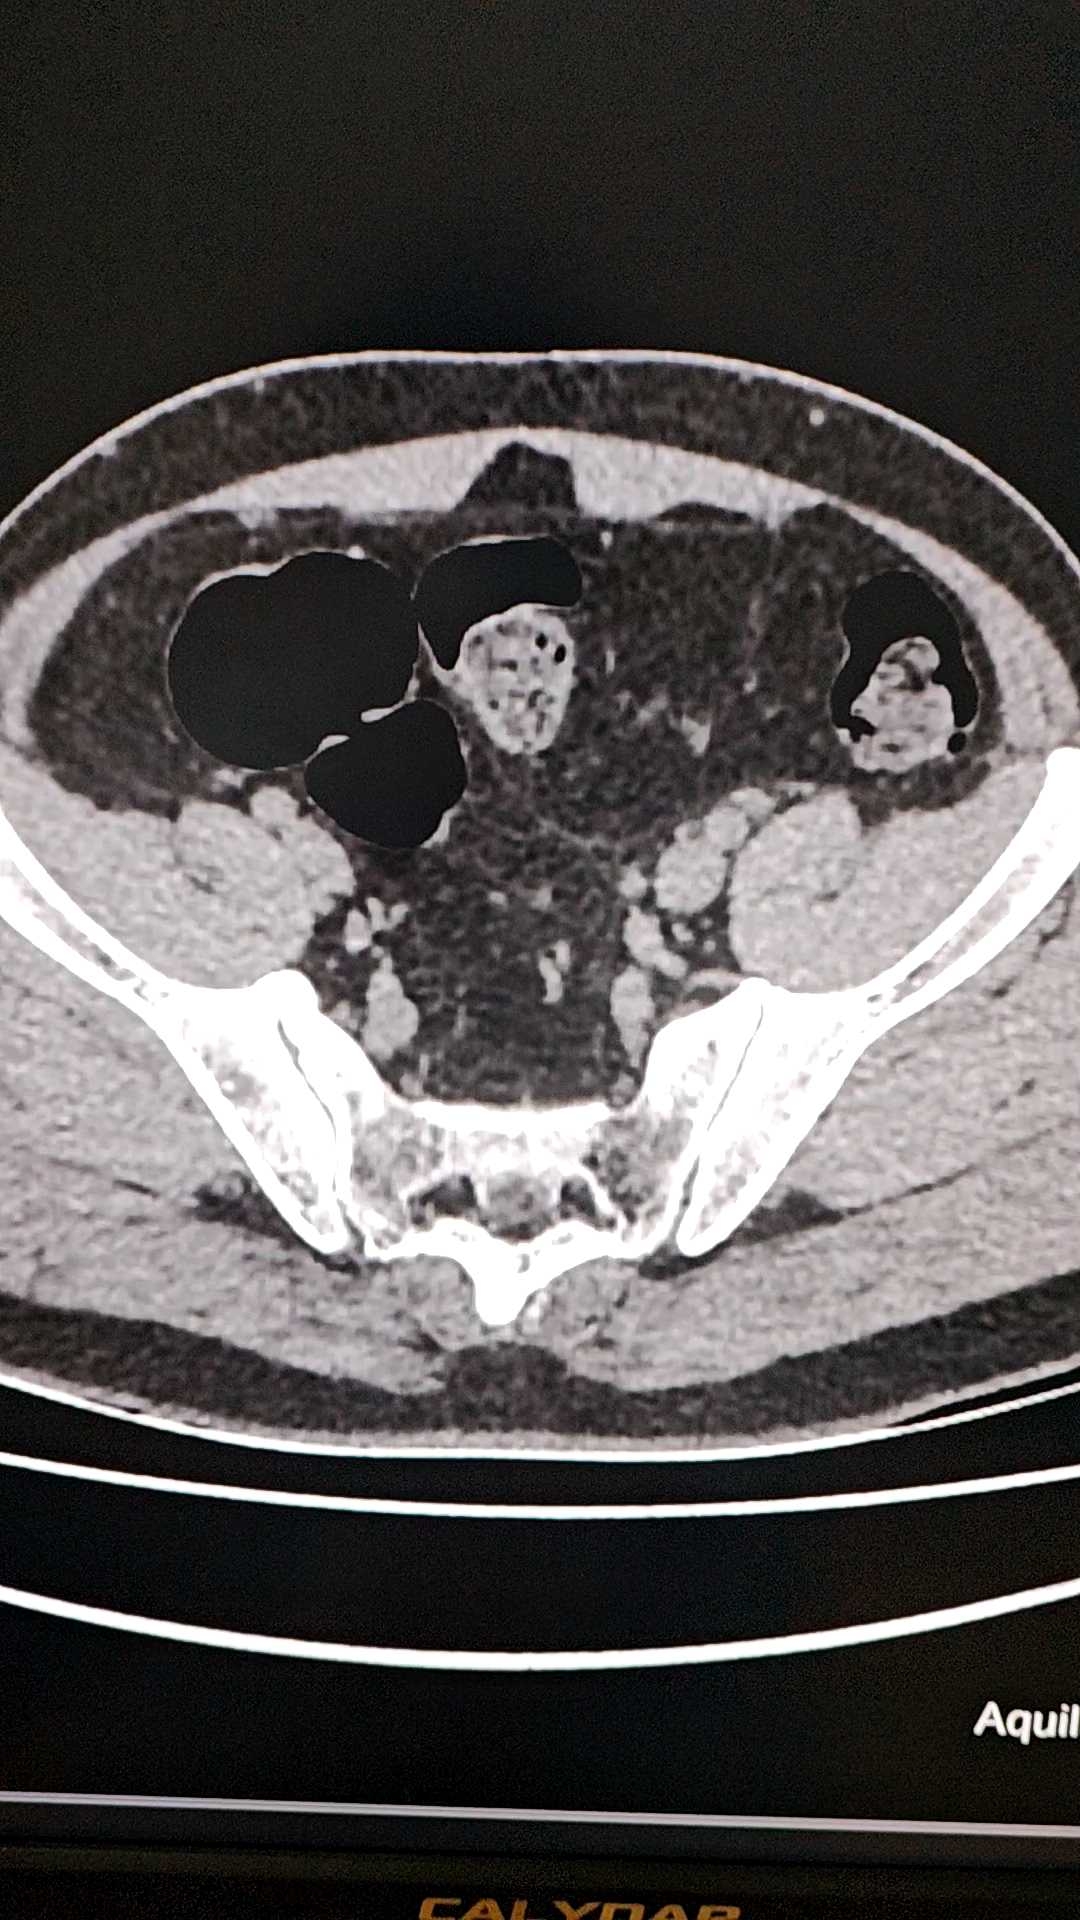

男,70岁,体检发现盆腔包块,无临床症状。ct值约45Hu,增强后轻微强化。